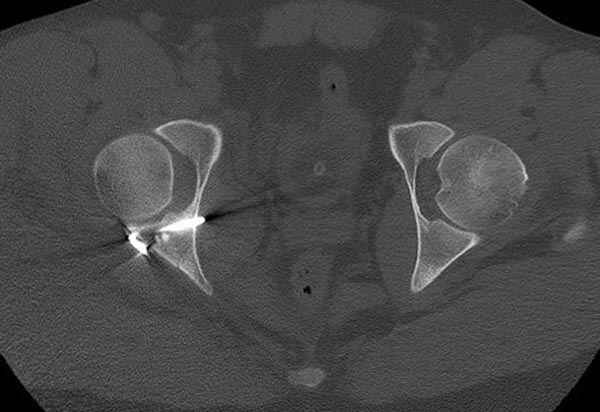

11:50 больной в послеоперационной, рентгенограмма N7, компьютерная томограмма в тот же день N8-10

На рисунке N1 предоперационный план лечения ложного сустава шейки бедра- линия ложного сустава, угол и направление введения импланта, клиновидная остеотомия в градусах и миллиметрах, второй снимок после коррекции, расчет, на сколько удлиняется конечность и размеры импланта;

N3 рисунок окончательный снимок, после операции моя рентгенограмма должен выглядеть примерно как эта картина. На N4 снимке клин перед удалением; N5 послеоперации 3 нед.; N6 окончательная рентгенограмма.